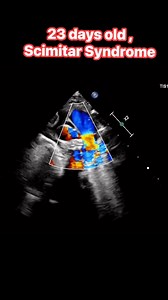

Scimitar Syndrome 的热门建议 |

Scimitar - Coronary Sinus

On Fetal Echo